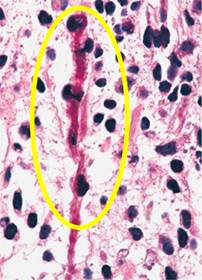

Se procedió a toma de biopsia por incisión y en el estudio histopatológico se establece que se trata de rabdomiosarcoma embrionario variedad tipo botrioide (Figura 5); por la clasificación del TNM, se consideró T2 N0 M0, etapa clínica III de riesgo intermedio.

Figura 5: Zonas sólidas con células redondas y fusiformes con núcleos oscuros hipercromáticos con mitosis atípica (rabdomioblastos).